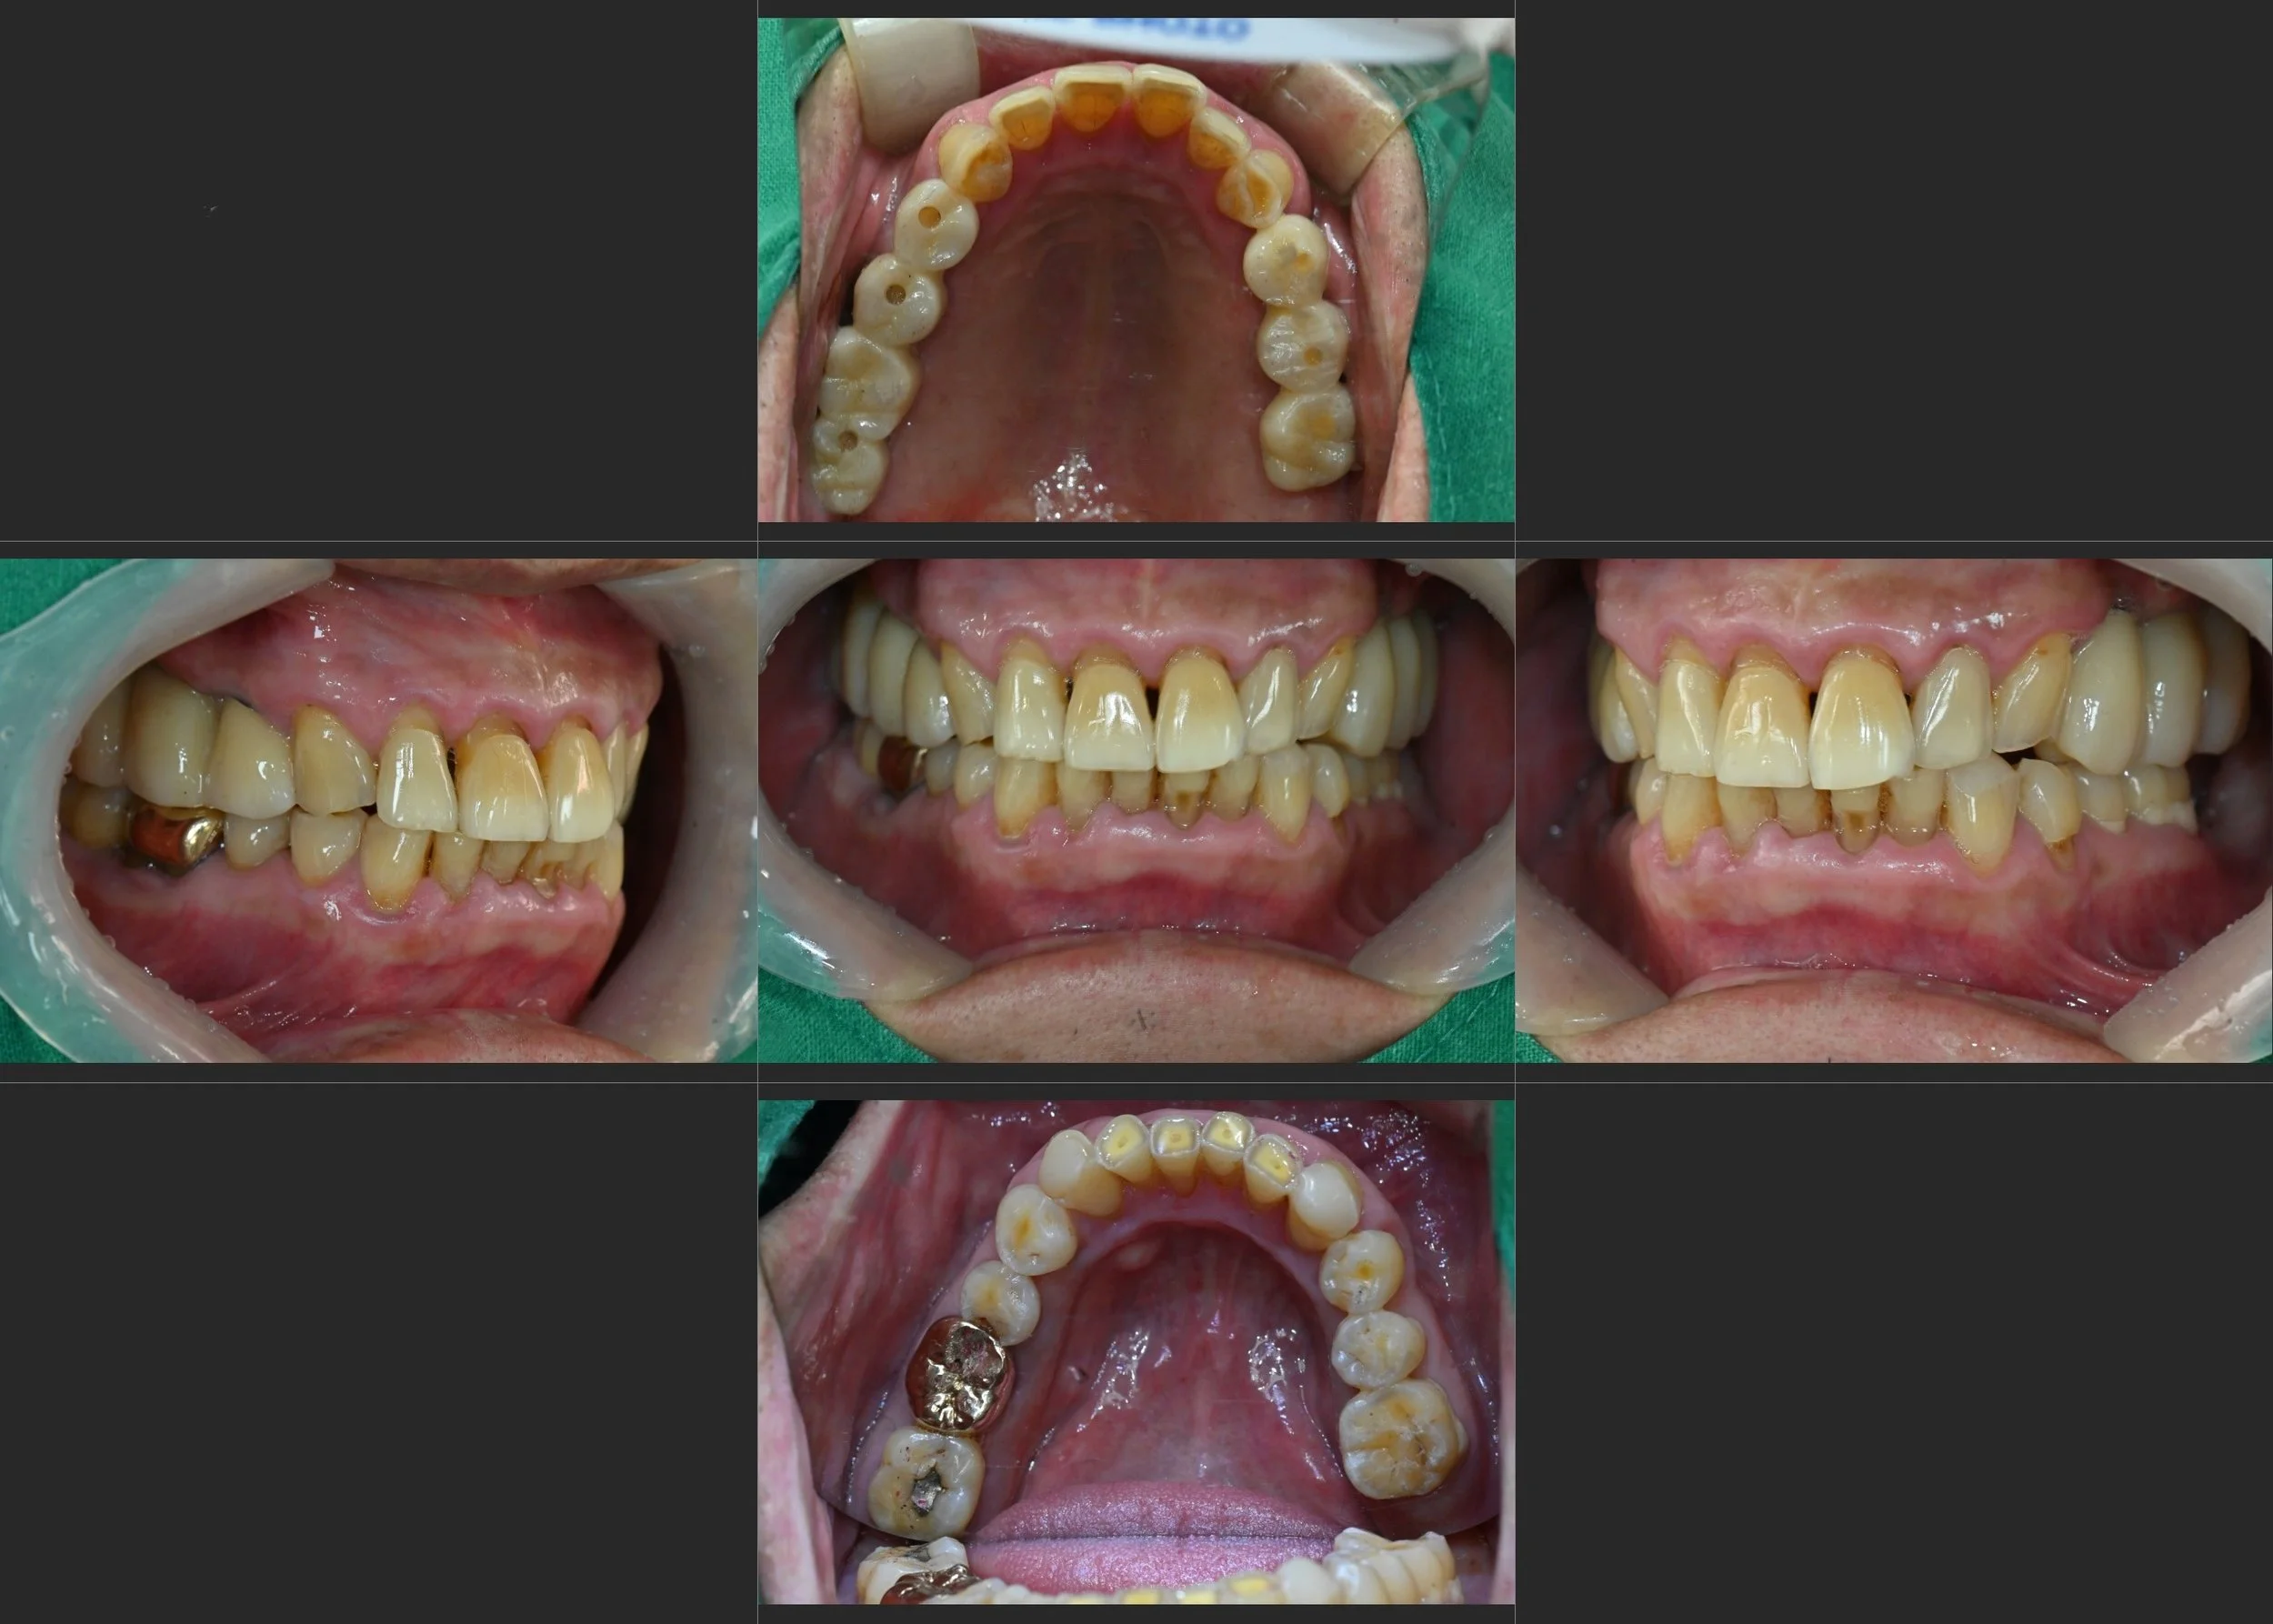

INTRA ORAL - AFTER

Previously damaged teeth were restored where feasible,

while severely worn anterior teeth were preserved with a maintenance-oriented approach.

Through controlled occlusal vertical augmentation and mandibular anterior repositioning,

excessive overjet and overbite were reduced,

anterior guidance was re-established,

and left–right occlusal balance was improved to support long-term functional stability.